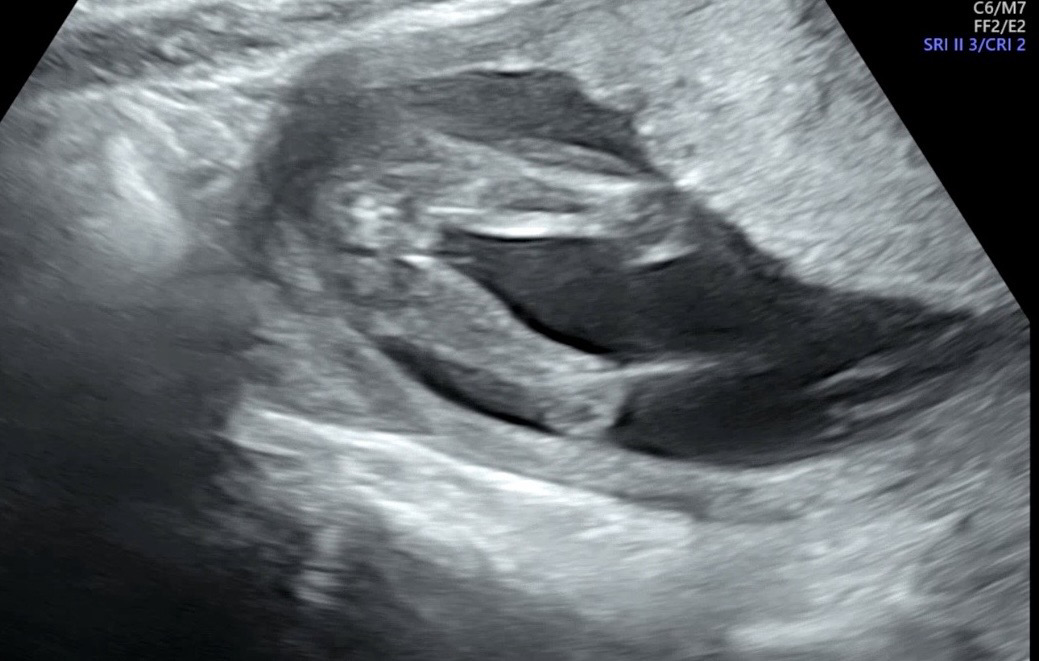

16주 초음파 성별 봐쥬세용

성별 뭔거 같으신가여~~??